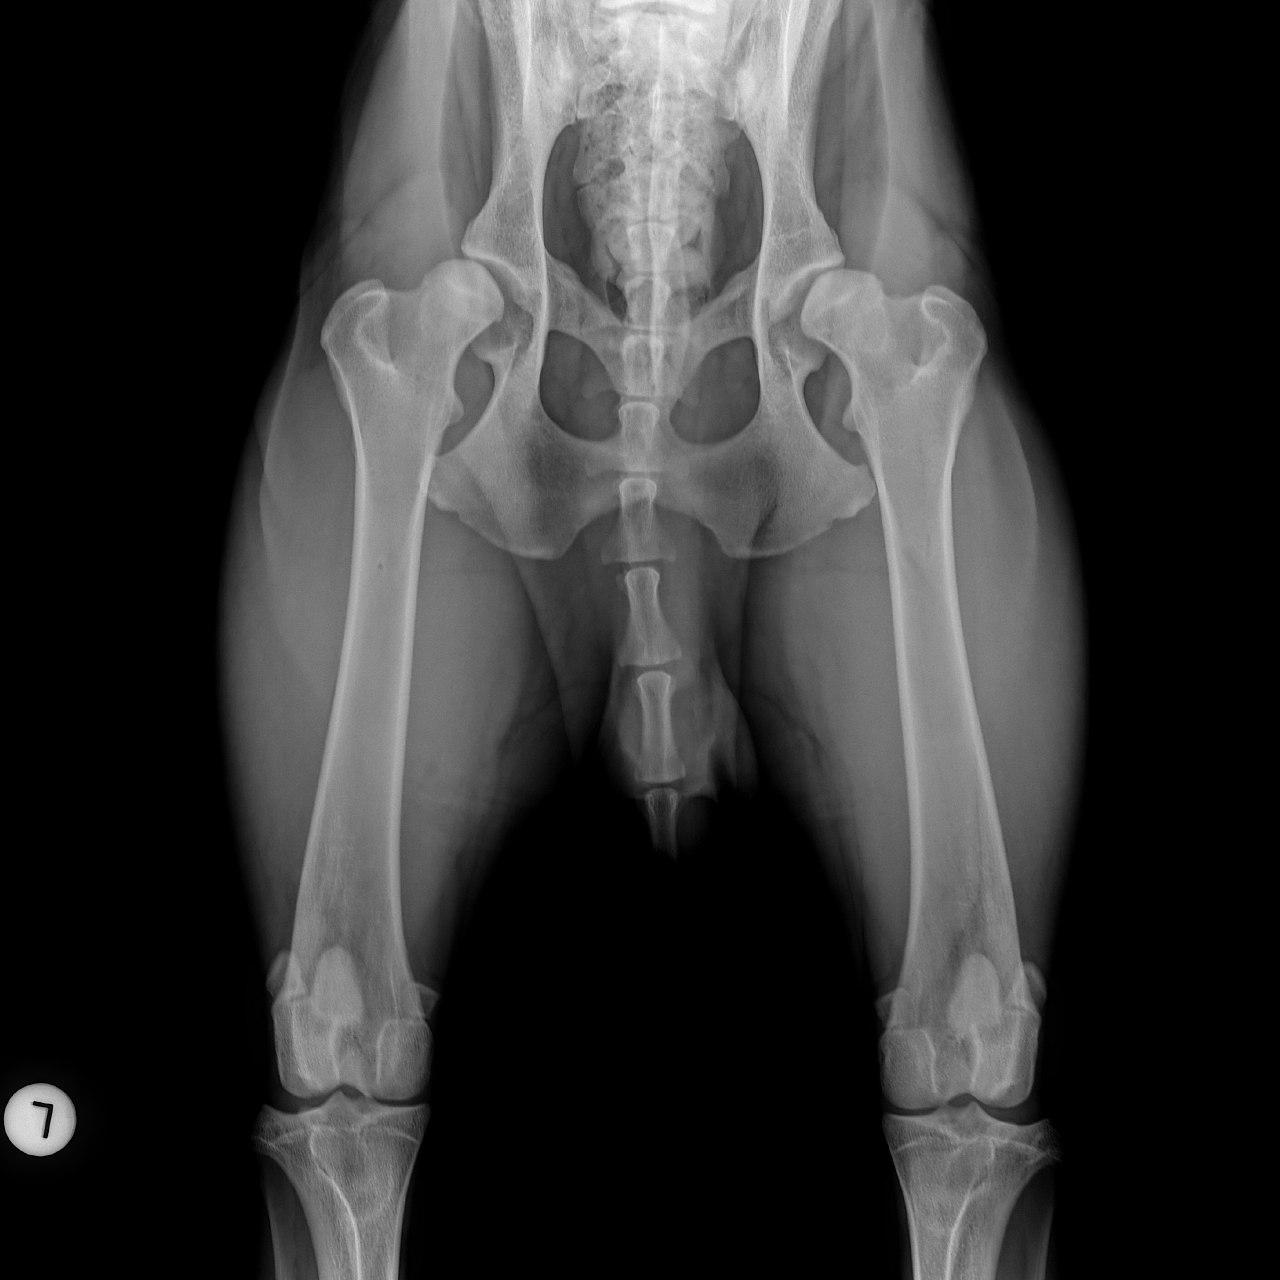

Mit der HD ist das so ne Sache..... die Vererbung spielt eine sehr große Rolle, ja. Aber bei unserer Peggy Zb ist es so, dass mehrere Generationen nachweislich HD und ED frei sind und auch frei von Spondylosen. Als einziger Hund überhaupt in der gesamten Zucht hat unsere Dame alles mitgenommen, was zu kriegen war;(: sie hat nicht nur schwere HD, weil ihre Hüfte viel zu locker ist, sondern dadurch bedingt am rechten Knie bereits schwere Arthrose und hinten links eine Sehenschwäche (durch Überlastung), weshalb sie dort durchtrittig ist. Und als würde das alles nicht schon vollkommen reichen, wurden aktuell auch noch mehrere heftige Spondylosen diagnostiziert;(. An einer Stelle ist sogar schon etwas abgebrochen8|.

Trotzdem hat er mittlere HD und ich fühle mich auch irgendwie total schuldig.